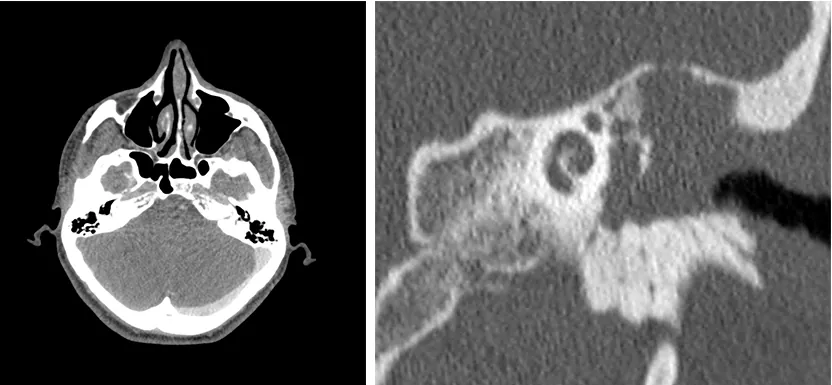

• Trombosis del seno sigmoides, que es una circunvalación que hace la vena yugular interna en la pared posterior de la cavidad mastoidea y que puede verse afectada por el colesteatoma y progresar hacia el torrente sanguíneo o a la cavidad craneal, provocando complicaciones fatales.

• Rotura del tegmen tímpani, que como hemos descrito anteriormente es la pared ósea que separa el oído medio de la fosa craneal media. Su erosión y rotura puede provocar meningitis y abscesos cerebrales de evolución mortal en ocasiones.

Sup. Trombosis del seno sigmoides derecho.

Inf. Lesión de partes blandas expansiva con destrucción del tegmen tímpani.